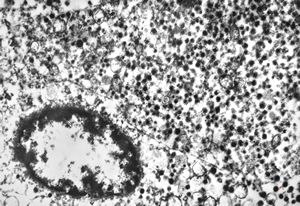

chylomicrons … negative staining